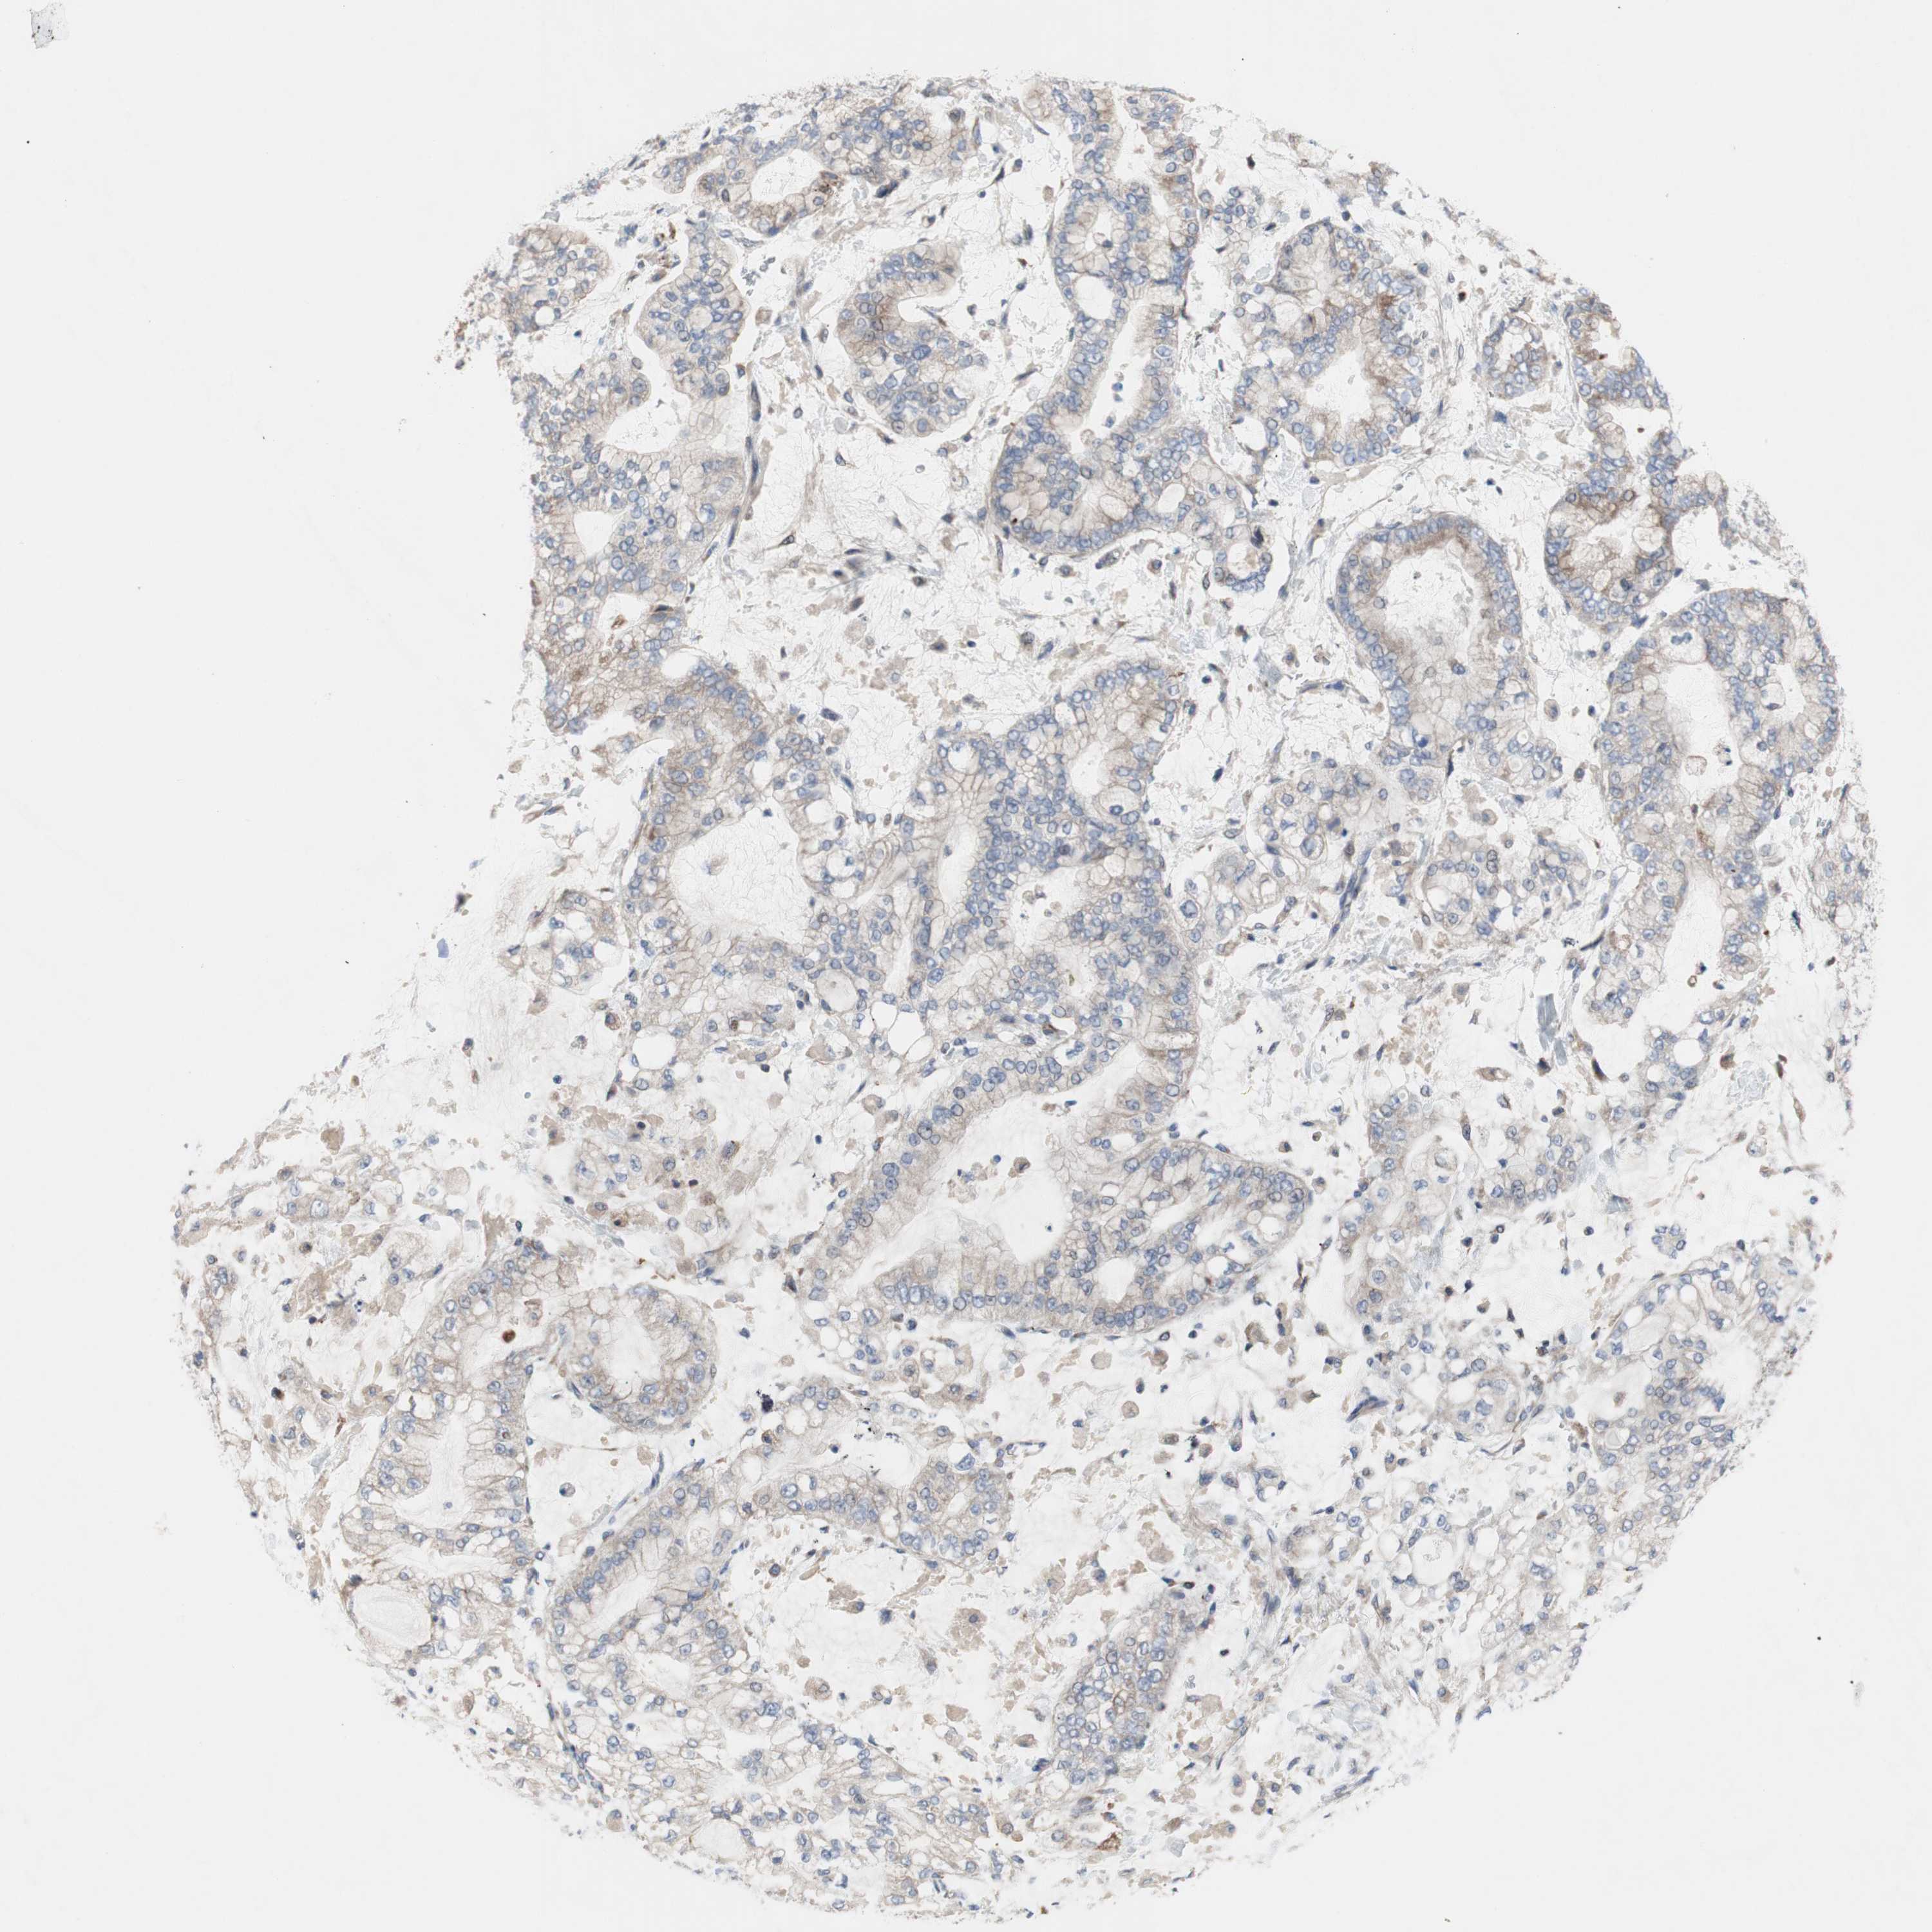

STOMACH CANCER - Protein expressioni

A mouse-over function shows sample information and annotation data. Click on an image to view it in a full screen mode. Samples can be filtered based on level of antibody staining by selecting one or several of the following categories: high, medium, low and not detected. The assay and annotation is described here.

Note that samples used for immunohistochemistry by the Human Protein Atlas do not correspond to samples in the TCGA dataset.

Antibody stainingi

Antibody staining in the annotated cell types in the current human tissue is reported as not detected, low, medium, or high, based on conventional immunohistochemistry profiling in selected tissues. This score is based on the combination of the staining intensity and fraction of stained cells.

Each image is clickable and will lead to virtual microscopy that enables deeper exploration of all samples and also displays staining intensity scores, fraction scores and subcellular localization as well as patient and tissue information for each sample.

Antibody HPA009295

Staining

High

Medium

Low

Not detected

Intensity

Strong

Moderate

Weak

Negative

Quantity

>75%

75%-25%

<25%

None

Location

Nuclear

Cytoplasmic/membranous

Cytoplasmic/membranous,nuclear

Adenocarcinoma, NOS